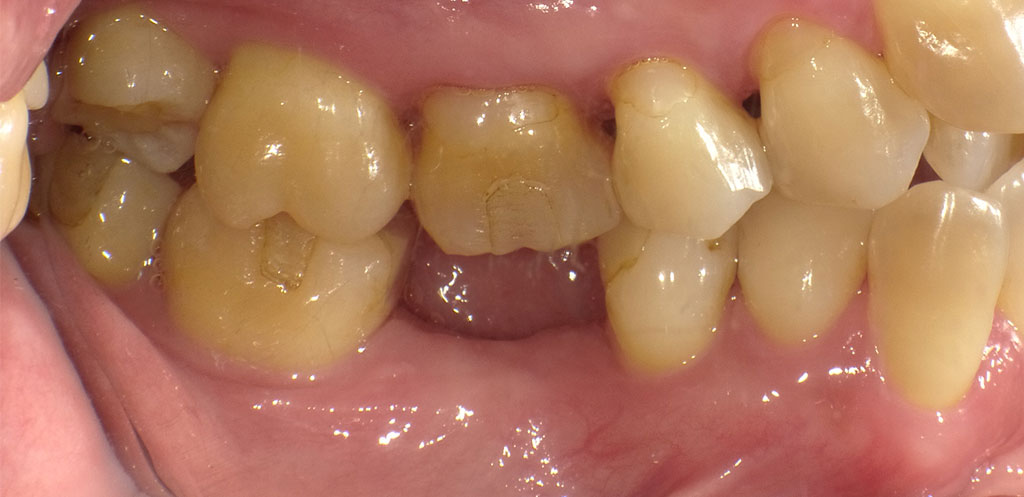

Before2

50代女性。他院にて抜歯しそのままにしていたため、インプラント治療を希望されてご来院されました。

フラップレス手術にて、右下6番の骨にインプラントを埋め込みました。インプラントと骨がしっかり結合するまで3ヶ月待ち、インプラントの上に人工の歯を被せる治療を行いました。